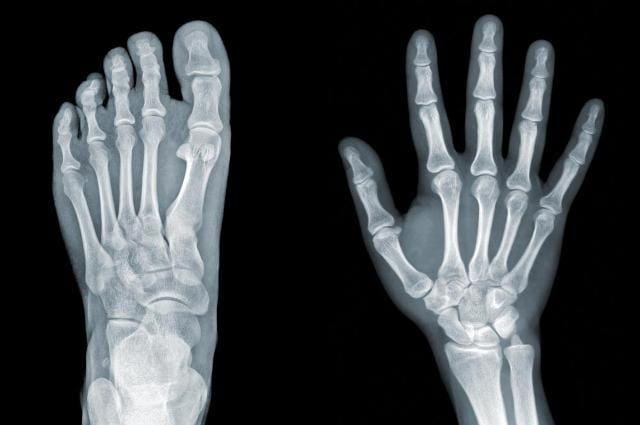

2. Lebih dari setengah jumlah tulang di tubuh ditemukan di kaki dan tangan

Tulang terbentuk menjadi beragam bentuk dan ukuran, dan tidak tersebar secara merata di seluruh tubuh. Beberapa organ tubuh tersusun dengan jumlah tulang lebih banyak dibanding organ lainnya. Hal itu bisa ditemukan pada tangan dan kaki manusia.

Masing-masing tangan punya 27 tulang, sementara masing-masing kaki punya 26 tulang, sehingga secara total keduanya tersusun atas 106 tulang. Kesimpulannya, lebih dari setengah jumlah tulang penyusun tubuh ada di tangan dan kaki.